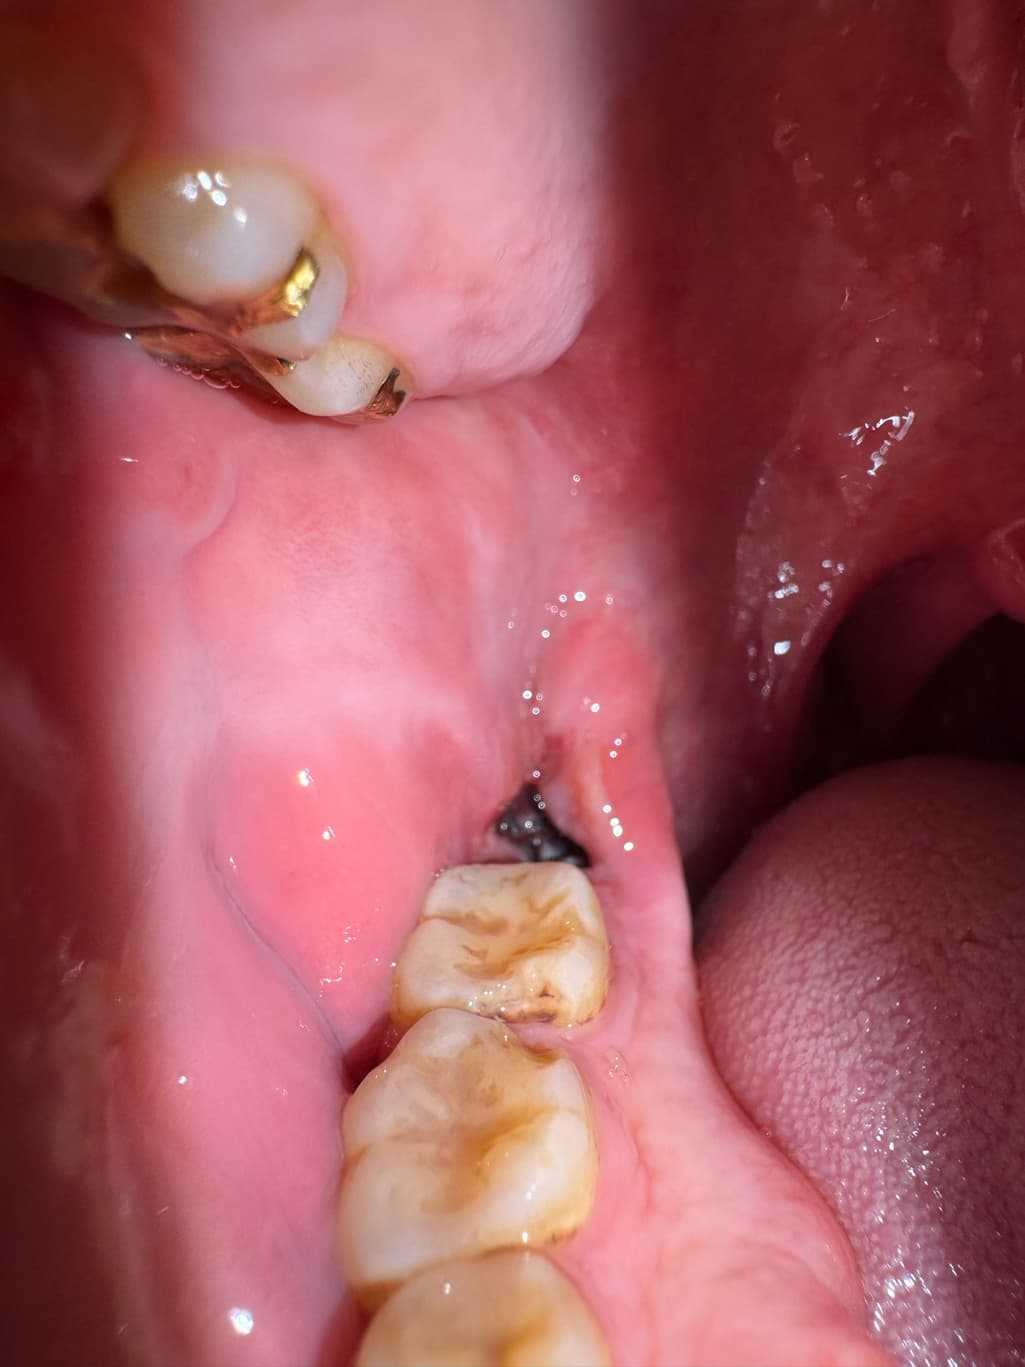

사랑니 발치 2일차, 지금 상태는 괜찮은건가요

음식물이 약간 끼어서 주사기로 가글액 분출해서 빼냈는데 약간 혈병이 씻겨나간건가 괜히 걱정되네요. 혈병이 굳어서 자리잡는건 언제부터인가요? 음식물을 섭취해야하는데 맘놓고 먹지도 못하겠어서요 불안해서…

사진상으로는 특별히 문제가 보이진 않습니다. 붓기는 조금 더 빠져야 하며 관리만 잘해주시면 됩니다.

지혈도 잘되고 발치한곳도 잘 아물고 잇는건 같습니다. 자극만 가지 않도록 해주시면될것같습니다.

사진으로 봤을 경우 사랑니를 발제한 부위에 혈병이 잘 유지되고 있으며 문제가 없는 것으로 보입니다. 해당 부위를 자극하지 않는 것이 좋습니다.